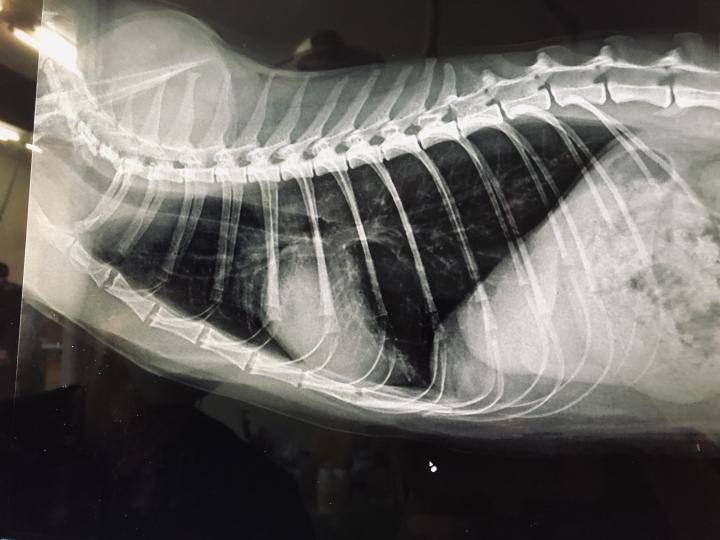

この先、レントゲンの画像あり

ご不快な方はここで🙇

ひなのレントゲン覚え

肺、胃共に問題なし